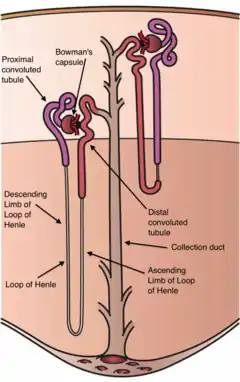

Gitelman syndrome (GS) is an autosomal recessive kidney tubule disorder characterized by low blood levels of potassium and magnesium, decreased excretion of calcium in the urine, and elevated blood pH.[1] The disorder is caused by genetic mutations resulting in improper function of the thiazide-sensitive sodium-chloride symporter (SLC12A3, also known as NCC, NCCT, or TSC) located in the distal convoluted tubule of the kidney.[1] The distal convoluted tubule of the kidney plays an important homoestatic role in sodium and chloride absorption as well as of the reabsorption of magnesium and calcium.[2]

Genetic mutations of NCC, lead to loss of function and subsequently, reduced transport of sodium and chloride via NCC. Secondary derangement of calcium, magnesium, and potassium concentrations are caused by secondary effects in the distal tubule and collecting duct. The effect is an electrolyte imbalance similar to that seen with thiazide diuretic therapy (which causes pharmacological inhibition of NCC activity).

Gitelman syndrome was formerly considered a subset of Bartter syndrome until the distinct genetic and molecular bases of these disorders were identified. Bartter syndrome is also an autosomal recessive cause of hypokalemic metabolic alkalosis, but it derives from a mutations of a number of genes that reduce NKCC2 activity. NKCC2 is found in the thick ascending limb of the loop of Henle.[3]